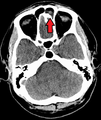

A computed tomograph showing infection of the ethmoid sinus

Maxillary sinusitis caused by a dental infection associated with periorbital cellulitis